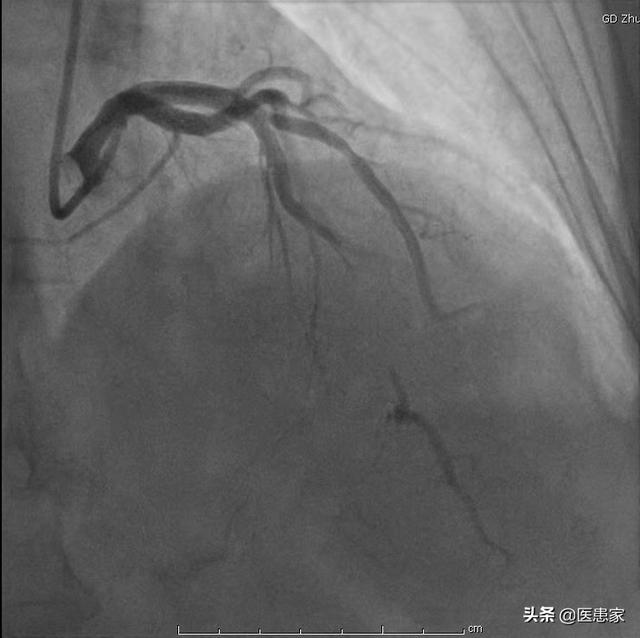

1.冠動脈造影は確かに冠動脈疾患の診断のゴールドスタンダードであり、冠動脈の様々な枝の狭窄病変の位置を明確に同定し、その範囲と血管全体の血液供給を推定できる動的検査である。しかし、この検査は大腿動脈または橈骨動脈を経由して行わなければならない侵襲的な検査であり、検査費用が相対的に高くつくので、この検査を受けるのに適さない患者もいる。

冠動脈造影は確かに信頼性が高く、精度の高い検査である。しかし、血管に損傷があれば、より多くの造影剤を注入する必要があり、ガイドワイヤーによる冠動脈の刺激は冠動脈の血管攣縮のリスクを高めることにつながるという欠点もある。

まず、冠動脈造影は単なる検査であり、冠動脈疾患の重症度を評価し、冠動脈疾患の治療効果を評価し、冠動脈疾患の有無を確認するための重要な検査であることを明確にしなければなりません。そのため、冠動脈疾患と診断された多くの患者さんにとって、冠動脈疾患の治療効果を明らかにするため、また冠動脈疾患の重症度を評価するために、冠動脈造影検査を選択し、状態を評価し、治療を指導しなければならないことがよくあります。

冠動脈造影とは何ですか?

冠動脈造影検査は、他のルーチン検査と違って、同様の検査に比べて患者に害を及ぼす可能性があるため、クリニックで気軽に行うことはできず、できることなら行わないのが原則である。

冠動脈造影検査は冠動脈疾患の診断を確定するためのゴールドスタンダードの一つであり、冠動脈狭窄の程度を明らかにする上で非常に重要な役割を果たしている。冠動脈のアテローム性動脈硬化症による冠動脈性心疾患患者にとって、現在の医療状況では、有効な治療法はなく、長期的な治療が必要であり、病状を安定させ、コントロールし、合併症の発生を減らすためには、定期的な治療と同時に、病状の変化のモニタリングと定期的な見直しに注意を払う必要があり、病状のコントロールの定期的な見直しと個別化されたプログラムの開発を遵守することは、かけがえのない役割を担っています。冠状動脈性心臓病の患者は定期的に見直すべきである。

冠動脈性心疾患とは、冠動脈の動脈硬化が原因で起こる心臓病で、冠動脈の狭窄や閉塞により虚血、低酸素、心筋細胞の壊死が起こる。冠動脈疾患の診断には、臨床症状、臨床検査、心電図、冠動脈CT、冠動脈造影などの総合的な判断が必要である。